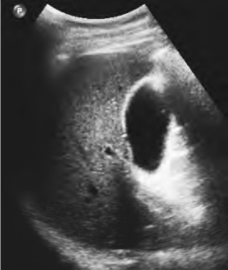

1.27.6六、肝囊肿